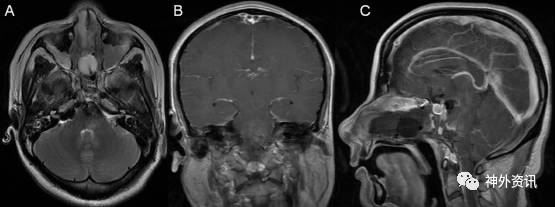

术后患者意识清,无吞咽困难及饮水呛咳,左眼轻度闭合不全,左侧鼻唇沟稍变浅,左眼球外展受限。右上肢肌力II级,右下肢肌力III级,左侧肢体肌力V级。予神经营养药等对症治疗。复查头颅MRI示肿瘤全切,未见明显残留(图4)。术后2周,体温正常,一般情况稳定,无脑脊液鼻漏。顺利出院。术后一月随访,右侧肌力等较前有明显改善。

图4. 术后头颅MRI:A)T2加权像、B)增强后冠状位和C)矢状位示未见明显肿瘤残留。